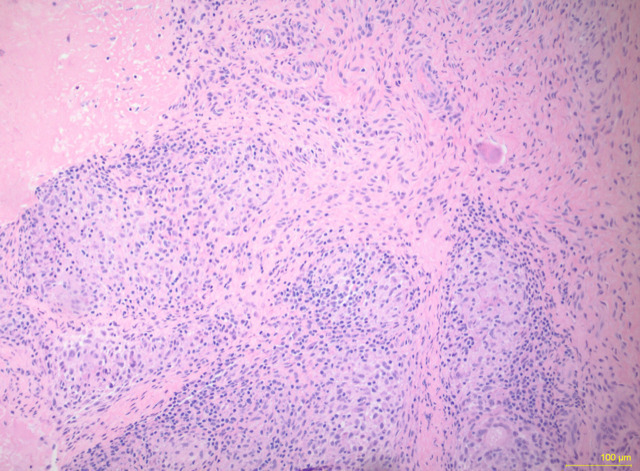

腕部结核分枝杆菌(TB)复合骨髓炎十分罕见,而多菌性结核骨髓炎则更为罕见。作者描述了一例不寻常的多菌性结核腕骨髓炎病例。病例患者的手腕上有两个隐匿生长的结节,病史长达 2.5 年。他接受了清创术,组织培养出了耐甲氧西林金黄色葡萄球菌、粪肠球菌,后来又发现了结核复合菌。他开始服用万古霉素、利福平、异烟肼、吡嗪酰胺和乙胺丁醇,症状有所改善。该病例强调了对骨髓炎的非典型表现进行广泛鉴别和全面检查的重要性。不常见病因的诊断对于明确治疗至关重要。

Wrist Mycobacterium tuberculosis (TB) complex osteomyelitis is rare, with polymicrobial TB osteomyelitis even more uncommon. The authors describe an unusual case of polymicrobial TB wrist osteomyelitis. The case patient presented with a 2.5-year history of 2 insidiously growing nodules on his wrist. He underwent debridement, and tissue cultures grew methicillin-resistant Staphylococcus aureus, Enterococcus faecalis, and, later, TB complex. He was started on vancomycin, rifampin, isoniazid, pyrazinamide, and ethambutol with improvement in symptoms. This case emphasizes the importance of a broad differential and thorough workup for atypical presentations of osteomyelitis. Diagnosis of uncommon etiologies is essential for definitive treatment.